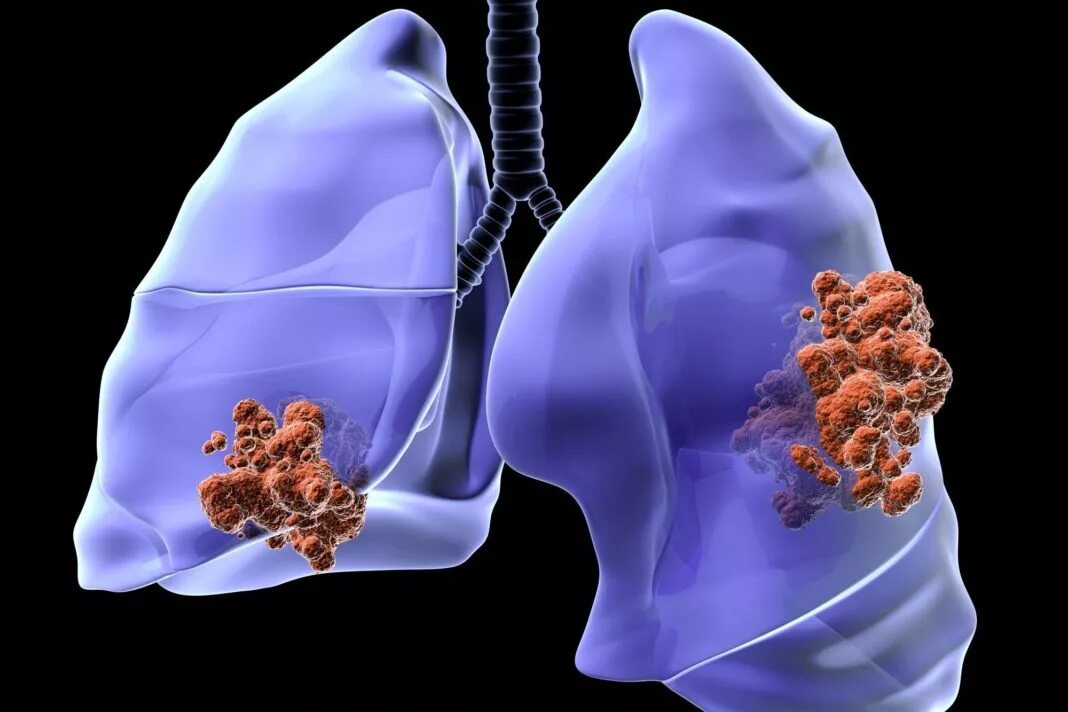

Онко легкие